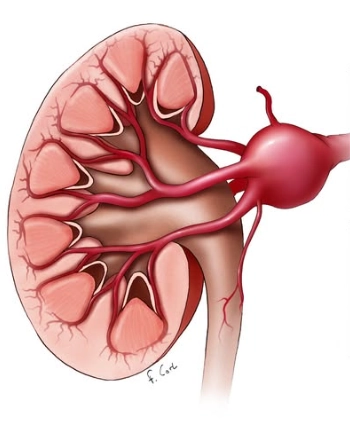

• Phình động mạch thận (Renal Artery Aneurysm - RAA)

• Giả phình động mạch thận (Renal Artery Pseudoaneurysm)